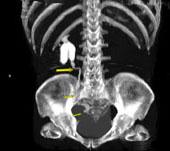

问题 男,55岁,尿频,尿痛伴低热乏力1个月。如图所示,下列说法正确的是 ( )

选项 A、左侧输尿管结核 B、左侧输尿管癌 C、右侧肾积水 D、膀胱变形 E、左侧输尿管多发性狭窄

答案 ACDE